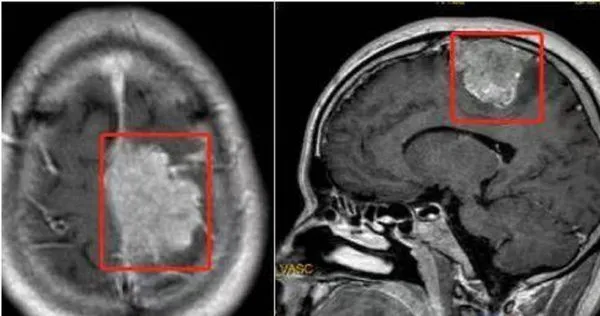

王某在醫院做頭顱磁振造影後,發現他的頭長了個矢狀竇旁腦膜瘤,且這個腫瘤直徑達到5.6公分,他之所以走路會「掉鞋」就是因為腫瘤壓迫到了神經,導致肢體偏癱、感覺障礙。人民醫院神經外科主任告訴他,只能手術切除,術後王某恢復良好,目前已痊癒出院。